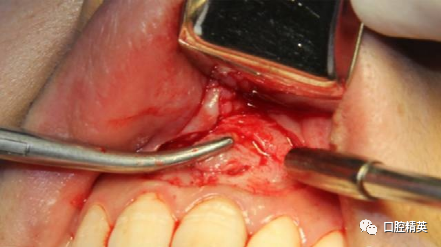

种植手机球钻轻打磨骨窝洞,直至暴露新鲜骨面。21根切倒充,玻璃离子充填。骨窝洞开血井,保证血供。

BIO-OSS骨粉混合PRF填补骨缺损。